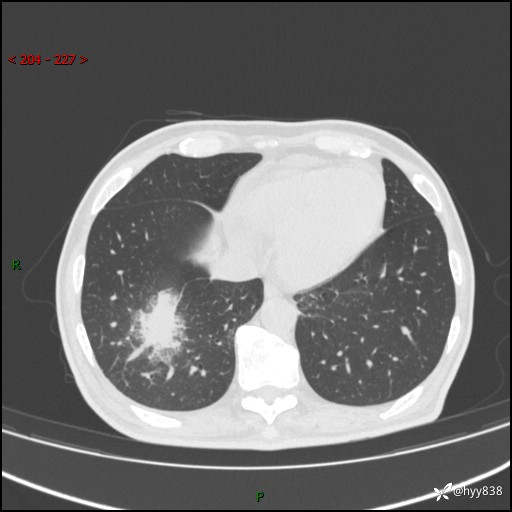

66岁/男,确诊髓系白血病5月,乏力伴气促半月。孤立结节,“晕”的厉害---结果公布~

【患者信息】:66岁/男

【主诉】:确诊髓系白血病5月余,乏力纳差伴气促半月

【现病史及既往史】:患者5月前无明显诱因出现牙龈出血,未重视,2024.5.10社区体检查血常规发现全血细胞减少,后自觉活动后心慌气促,无发热、头痛、咳嗽咳痰、胸痛等,为进一步诊治来我院,门诊以“全血细胞减少”收入,入院后完善相关辅检入院后确诊急性髓系白血病。于2024.06.11给予阿扎胞苷+维奈克拉化疗,给予输血、升白细胞、抗过敏、止血治疗,化疗后粒细胞缺乏,转入层流病房,出现发热,予以抗感染(头孢唑肟、莫西沙星、美罗培南)、抗真菌(卡泊芬净、氟康唑)、利尿、调脂、利胆、护心、护胃、调节免疫(羟氯喹、白芍总苷)、通便、调节胃肠道菌群、营养支持等对症治疗,出院时患者牙龈出血、咳嗽咳痰、腹胀、便秘等不适较前好转,复查血常规提示白细胞计数升高,要求出院,建议继续住院观察,但患者仍要求出院,予以办理。2024-08-06到我院规律化疗,2024-08-08给予阿扎胞苷+维奈克拉化疗,给予输血、升白细胞、抗过敏、止血治疗,化疗后粒细胞缺乏,转入层流病房,出现发热,予以护心、护胃 、营养支持等对症治疗,好转后出院。院外自行停用维纳克拉。半月前患者无明显诱因出现乏力、纳差、活动后气促,无心慌、胸闷,无咳嗽、咳痰,无畏寒、发热等不适,现患者为求进一步诊治来我院,门诊以“急性髓系白血病”收入院。 发病以来,患者精神、饮食欠佳,睡眠一般,大小便如常,体力明显下降,体重无明显减轻。

【检查】:胸部CT平扫